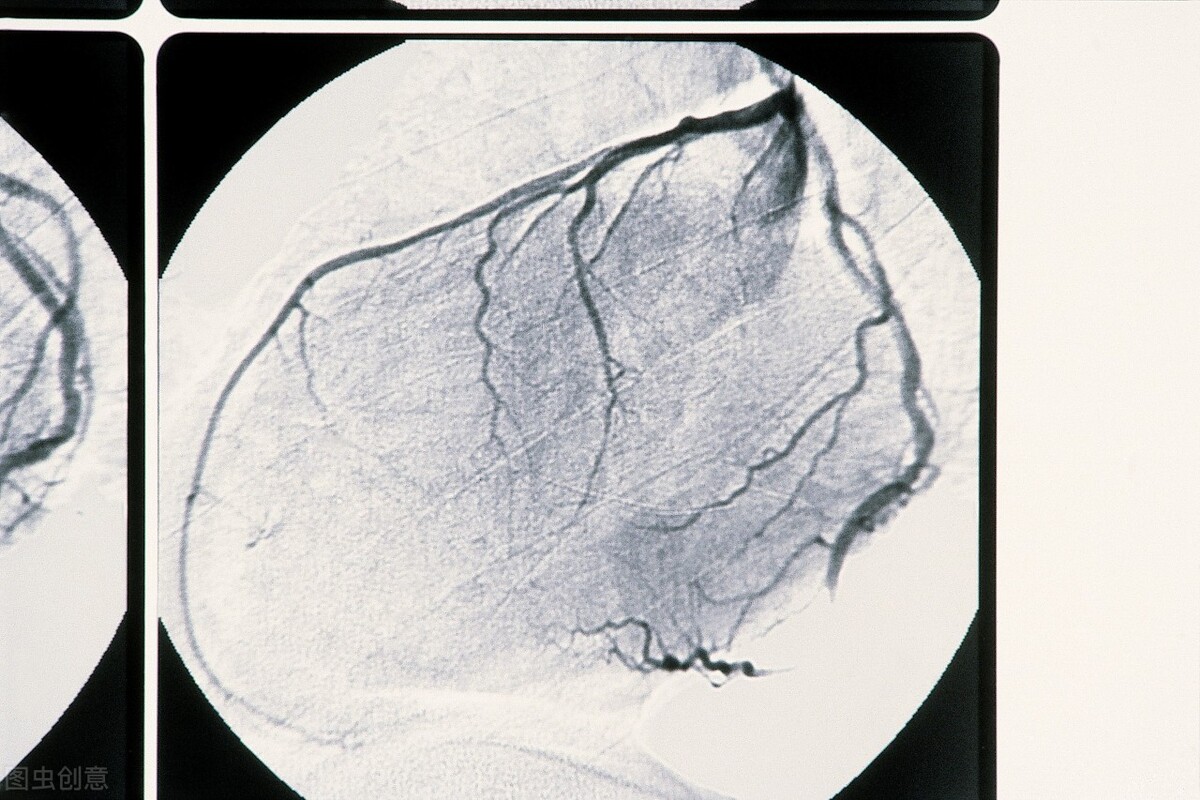

当做冠脉CT时,发现冠脉狭窄后,还要做平板心电图、心脏超声、心脏核素显像、冠脉造影等检查。看是不是真的狭窄,狭窄到了什么程度,狭窄是否造成了严重的心肌供血不足。